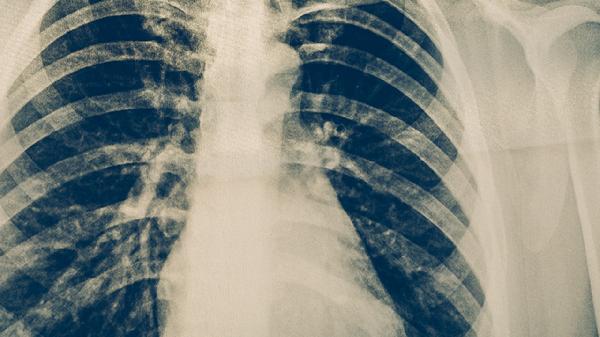

肺結(jié)核咳血的危害

肺結(jié)核咳血可能提示病情進(jìn)展或并發(fā)癥,需警惕大咯血窒息、感染擴(kuò)散等風(fēng)險(xiǎn)。肺結(jié)核咳血的危害主要有病灶擴(kuò)大、繼發(fā)感染、貧血、氣道阻塞、心理負(fù)擔(dān)等。

肺結(jié)核咳血患者需絕對(duì)戒煙,保持室內(nèi)空氣濕潤,食用溫涼流質(zhì)飲食。大咯血時(shí)立即禁食并急診處理,日常避免劇烈咳嗽動(dòng)作。嚴(yán)格完成6-9個(gè)月抗結(jié)核療程,定期復(fù)查胸部CT評(píng)估病灶,咯血超過50毫升/次或出現(xiàn)呼吸困難需即刻就醫(yī)。